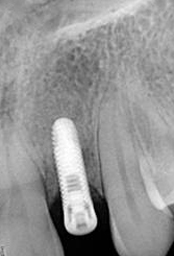

X-ray of Implant + Abutment

Single Tooth Implant

X-ray of Implant +

Abutment + Prosthesis

Placement of Bone Grafting

Abutment+ Prosthesis